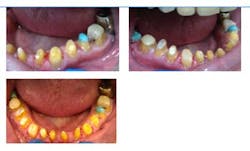

Fig. 5: Intraoral photographs, temporaries

The PVS matrix was then used to build up the occlusal surfaces posterior teeth and incisal edges of anterior teeth in the mandibular arch with composite and open his bite 3 mm. The patient was kept in these temporaries for five months. The patient would return to the office once a month to assess his TMJ and occlusion. Every month, the patient denied TMJ symptoms.